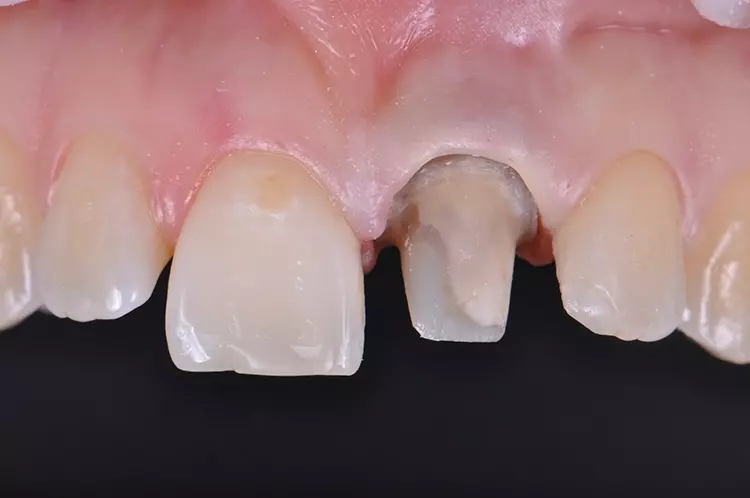

Im Rahmen des Erstgespräches berichtete die junge Patientin von einem Sturzereignis, bei dem der Schneidezahn frakturierte. Ihr damaliger Zahnarzt führte eine Wurzelkanalbehandlung durch und versorgte den Zahn mit einer Krone aus Lithiumdisilikat. Das anfänglich sehr ansprechende ästhetische Behandlungsergebnis hätte sich jedoch nach der Eingliederung mit der Zeit verändert und die Patientin stellte eine zunehmende Verfärbung der Frontzahnkrone fest (Abb. 2 und 3).

Dies kann aus einer nachträglich eingetretenen Verfärbung des devitalen Zahnes resultieren. Durch die sehr hohe Transluzenz der Glasphase einer Lithiumdisilikat-Restauration kann die dunkle Stumpffarbe durchschlagen und zu einem ästhetisch störenden „Grauschleier“ führen. In einem intensiven Beratungs- und Aufklärungsgespräch wurden der Patientin die Schwierigkeiten und Herausforderungen einer Einzelzahnkrone in der ästhetischen Zone bei einer hohen Lachlinie mit Exposition der Gingiva dargestellt.

Manche Details wie die Verfärbung der Gingiva wären nicht korrigierbar und verringerten die Vorhersagbarkeit eines optimalen ästhetischen Resultates. Die Neuversorgung dient der Verbesserung der ästhetischen Situation, eine perfekte Kopie des Zahnes 11 wird nicht zu erzielen sein, da die verfärbte Wurzel bestehen bleibe.

Trotz der aufgeführten Risiken und Unwägbarkeiten wünschte die junge Patientin eine Neuversorgung des Zahnes, um eine bestmögliche Ästhetik zu erreichen. Gleichzeitig sollten ihre natürliche Zahnfarbe und die individuelle Zahnstellung nicht verändert werden.